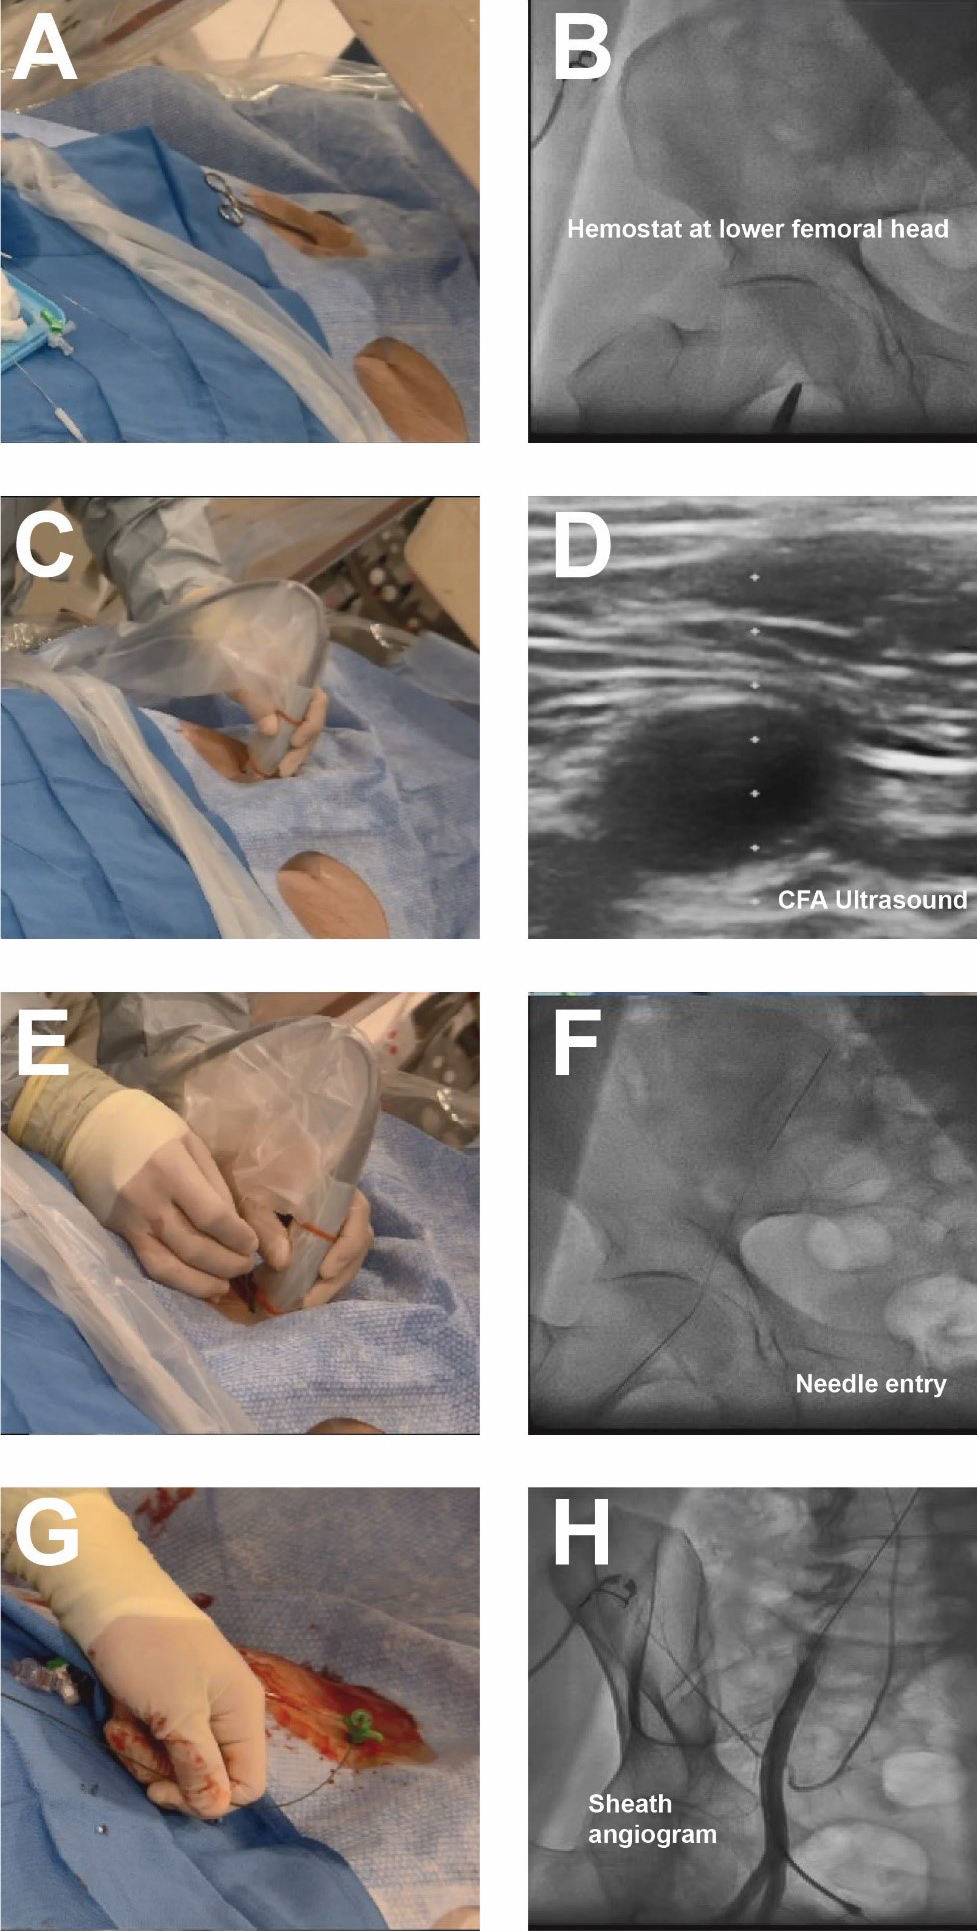

Contemporary femoral access should utilize all available techniques and adjunctive information available to reproducibly achieve vascular access with the lowest complication rate possible [18]. With the patient supine on the catheterization table, anatomic landmarks should be assessed. In patients with a large body mass index, retraction of the pannus can facilitate vascular access as well as hemostasis and closure. Placement of a radiopaque marker (hemostat) should be utilized in conjunction with fluoroscopy to assess the lower edge of the femoral head (Fig. 2). This location can be marked with a sterile pen and may help avoid high puncture. Ultrasound should then be performed to assess the ideal entry point for CFA access. The ultrasound probe can initially be placed perpendicular to the patient at the location of the lower edge of the femoral head as previously identified. Prior to attempting access the operator should assess the femoral artery anatomy including the location of the CFA bifurcation into SFA and PFA and evaluate for any major branch vessel, areas with severe calcification or obstructive peripheral arterial disease that should be avoided (Figs. 3,4). Longitudinal assessment of the CFA as it dives into the pelvis can also help the operator avoid high access, as well as visualization of the femoral head. Once the ideal target area of vascular access has been located with the ultrasound probe, careful attention should be given to any manipulation of the ultrasound probe. The ultrasound probe should be static and maintained straight without any tilting or angulation. Skin puncture with the access needle should occur 1–2 cm distal to the probe while aligned with the center marker on the probe and approximately 30–45 degrees. Steep angulations should be avoided as they can contribute to sheath or wire kinking. Following needle entry into the CFA, a J-tipped or micropuncture wire is introduced. Routine fluoroscopic assessment of needle entry location with the J-tipped/micropuncture wire in place (Fig. 2) should be performed to confirm that the needle entry is over the femoral head. If the needle entry is below or above the femoral head, this safety step allows for removal of the needle to reattempt access. If the needle entry site is satisfactory, then the wire can be advanced, however, tracking of the access wire should be pursued fluoroscopically when using the micropuncture wire as it can enter side-branches such as the inferior epigastric or deep circumflex iliac branches and cause perforations [28]. Following sheath insertion, femoral artery angiography [usually 30 degrees right anterior oblique (RAO) for right CFA access and 30 degrees for left CFA access] should be obtained to confirm safe access without complications, as well as help evaluate the anatomy and assess for tortuosity or peripheral arterial disease (Fig. 2). Occasionally additional angiographic projections may be required to confirm entry site. While femoral angiography can be performed through the micropuncture sheath, the latter provides limited opacification and has the risk for complications such as vessel dissection given that the injection is performed without assessment of hemodynamic waveform and the microcatheter sheath may be positioned against the vessel wall. Therefore, our suggested approach is that femoral angiography should preferably occur with the J-wire in place as such deflects the sheath from the vessel wall and maintains vessel control should complications occur. C-arm rotation can also be utilized to facilitate needle entry visualization. A standard setup for contemporary femoral access is shown in Fig. 5.

Fig. 3.Femoral access ultrasound. (A) Femoral artery ultrasound shows a trifurcation of the CFA and femoral vein to image right. (B) Superior to the CFA bifurcation is seen in an area amenable for vascular access. (C) CFA ultrasound noting significant luminal atherescolosis.